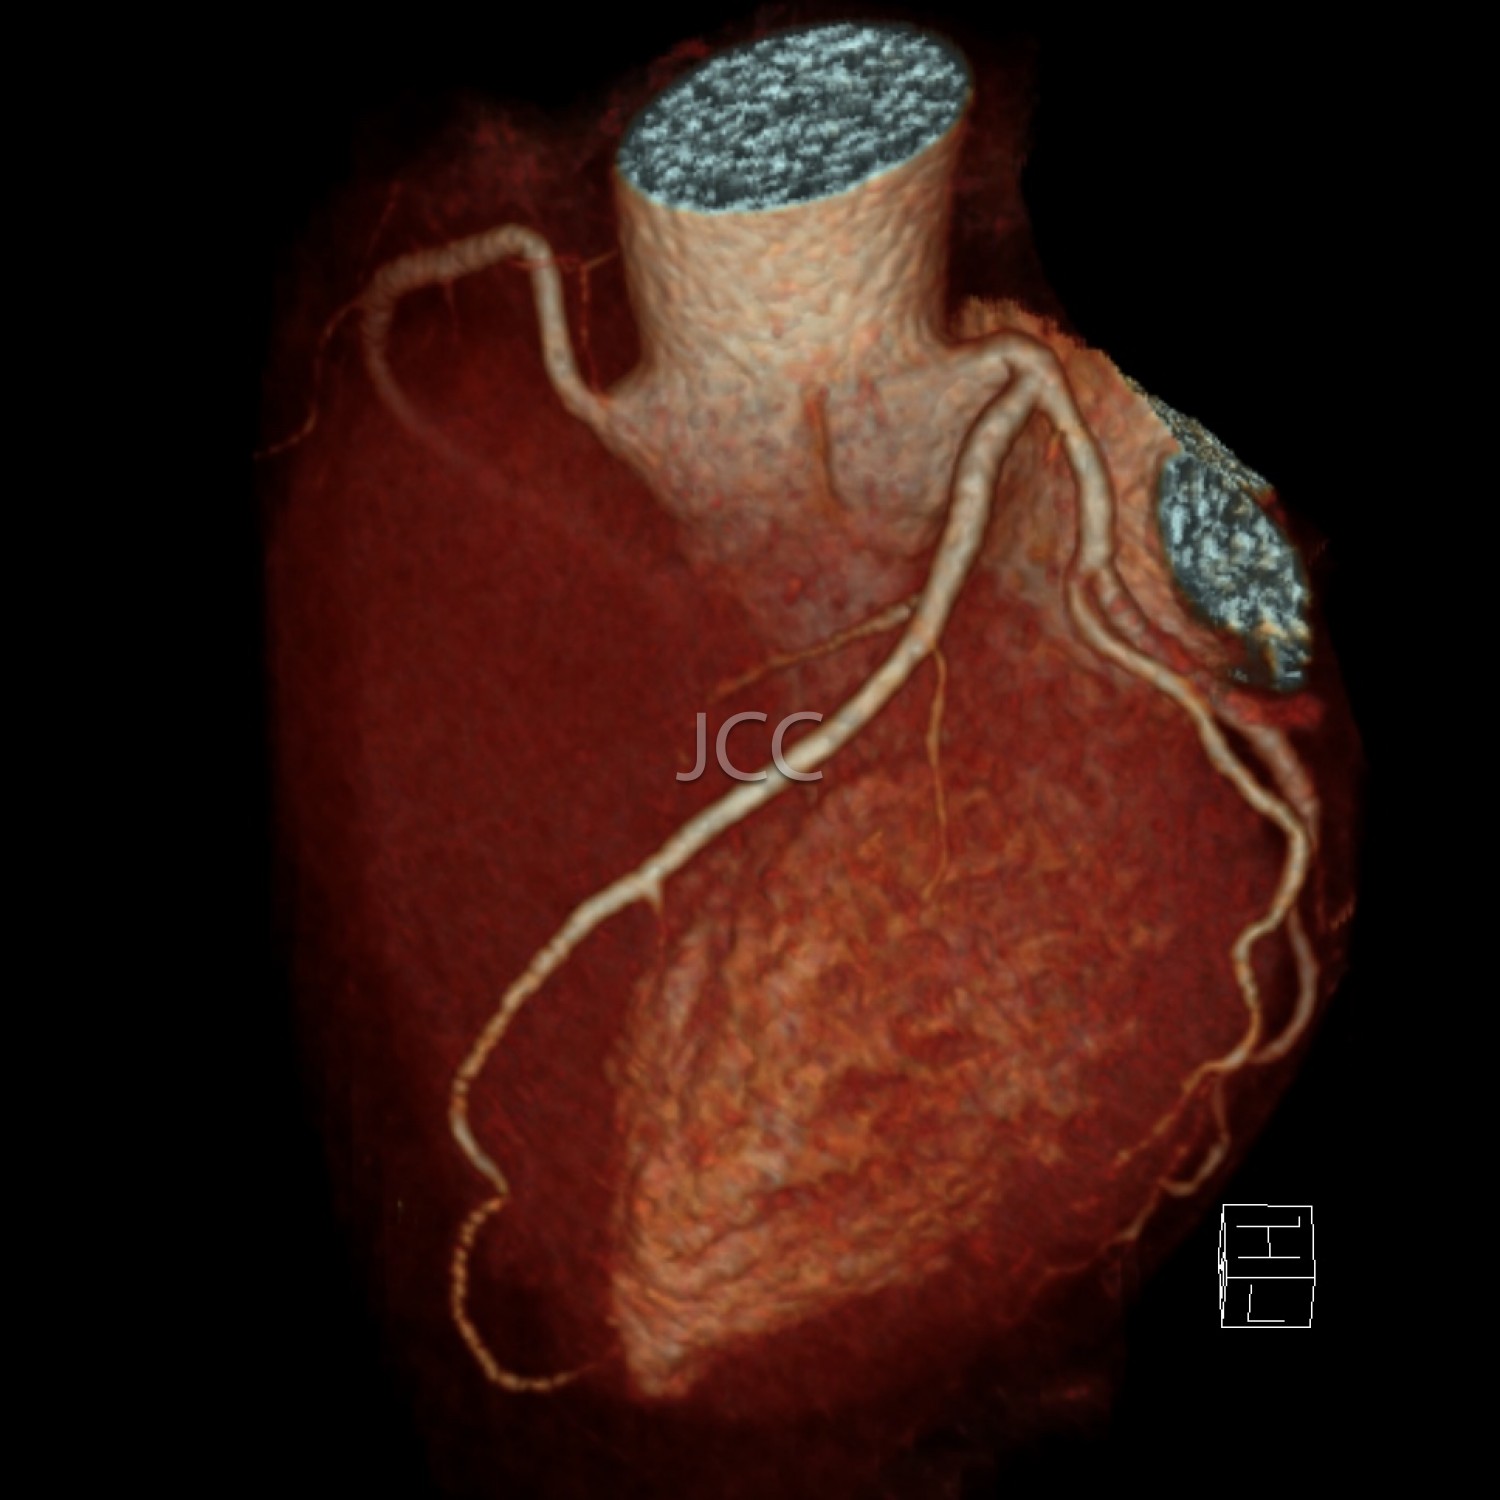

Tomografia Axial Computorizada - ANGIO TAC CORONÁRIAS

A Tomografia Axial Computorizada (TAC) - Dupla Energia - 256 cortes é uma técnica de diagnóstico que permite a avaliação de várias partes do corpo humano, incluindo pulmões, fígado, pâncreas, rins, coração, estruturas vasculares e estruturas ósseas.

Os nossos equipamentos são todos de multicorte permitindo avaliação em alta definição e baixa dose de radiação incluindo o estudo das coronárias.